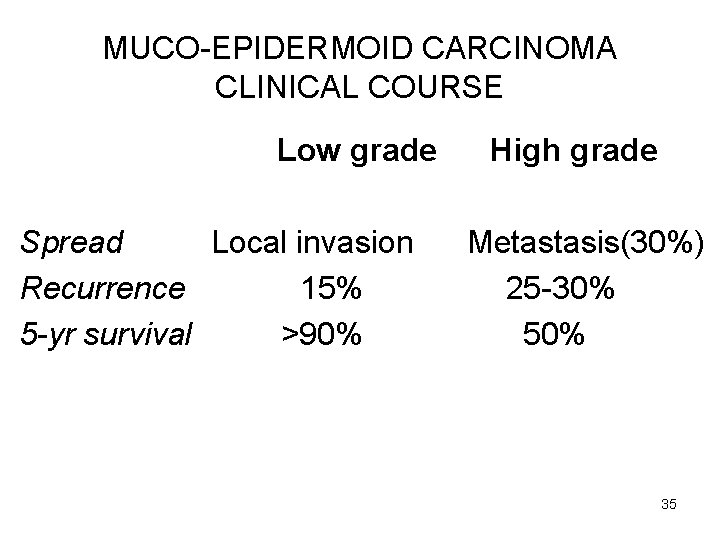

MUCO-EPIDERMOID CARCINOMA CLINICAL COURSE Low grade Spread Local invasion Recurrence 15% 5 -yr survival >90% High grade Metastasis(30%) 25 -30% 50% 35